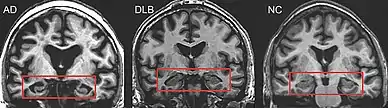

Direct laboratory-measurable biomarkers for DLB diagnosis are not known, but several indirect methods can lend further evidence for diagnosis.[25] The indicative diagnostic biomarkers are: reduced dopamine transporter uptake in the basal ganglia shown on PET or SPECT imaging; low uptake of 123iodine-metaiodobenzylguanidine (123I-MIBG) shown on myocardial scintigraphy; and loss of atonia during REM sleep evidenced on polysomnography. Supportive diagnostic biomarkers (from PET, SPECT, CT, or MRI brain imaging studies or EEG monitoring[124]) are: lack of damage to medial temporal lobe (damage is more likely in AD[116]); reduced occipital activity; and prominent slow-wave activity on EEG.[25]

Lewy pathology affects the peripheral autonomic nervous system; autonomic dysfunction is observed less often in AD, frontotemporal, or vascular dementias, so its presence can help differentiate them.[141] MRI scans almost always show abnormalities in the brains of people with vascular dementia, which can begin suddenly.[142]

DLB is distinguishable from AD even in the prodromal phase.[23] Short-term memory impairment is seen early in AD and is a prominent feature, while fluctuating attention is uncommon; impairment in DLB is more often seen first as fluctuating cognition.[143] In contrast to AD—in which the hippocampus is among the first brain structures affected, and episodic memory loss related to encoding of memories is typically the earliest symptom—memory impairment occurs later in DLB.[39][144] People with amnestic mild cognitive impairment (in which memory loss is the main symptom) may progress to AD, whereas those with non-amnestic mild cognitive impairment (which has more prominent impairments in language, visuospatial, and executive domains) are more likely to progress towards DLB.[145] Memory loss in DLB has a different progression from AD because frontal structures are involved earlier, with later involvement of temporoparietal brain structures.[144] Verbal memory is not as severely affected as in AD.[146]

PET or SPECT imaging can be used to detect reduced dopamine transporter uptake and distinguish AD from DLB.[57][149] Severe atrophy of the hippocampus is more typical of AD than DLB.[150] Before dementia develops (during the mild cognitive impairment phase), MRI scans show normal hippocampal volume. After dementia develops, MRI shows more atrophy among individuals with AD, and a slower reduction in volume over time among people with DLB than those with AD.[33] Compared to people with AD, FDG-PET brain scans in people with DLB often show a cingulate island sign.[33]